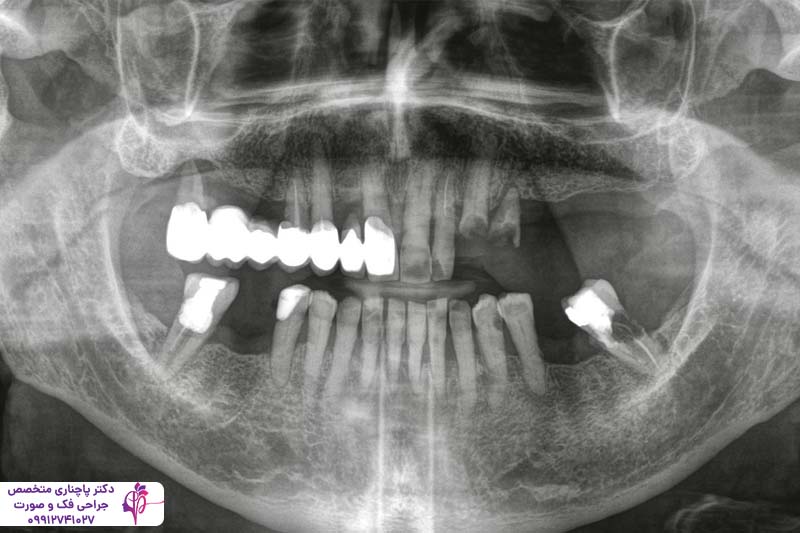

طول عمر ایمپلنت دندان به عوامل متعددی بستگی دارد و نمیتوان تنها با تکیه بر کشور سازنده، نتیجه قطعی گرفت. هر دو ایمپلنت دندان آلمانی یا سوئیسی در صورت کاشت صحیح، رعایت بهداشت دهان و انجام معاینات دورهای میتوانند بیش از ده تا بیست سال و حتی تا پایان عمر در دهان بیمار باقی بمانند. کیفیت بسیار بالای سطح ایمپلنت و جوش خوردن محکم و با ثبات با استخوان و طراحی اتصالات داخلی یکی از مهمترین دلایل ماندگاری بالای برندهای آلمانی و سوئیسی است.

در مقایسههای بالینی بین ایمپلنت دندان آلمانی و سوئیسی مشخص شد که هر دو گروه عملکرد قابل قبولی در مطالعات طولانیمدت دارند. یک سری تفاوتهای جزئی در سرعت جوش خوردن آنها یا میزان تحلیل استخوان فک در اطراف ایمپلنت دیده میشود که باز هم تاثیر چندانی روی طول عمر آنها ندارد. ولی انجام درمان توسط یک دندانپزشک حرفهای و با تجربه و کاشت صحیح و اصولی میتواند روی عمر طولانی ایمپلنتها تاثیر داشته باشد.